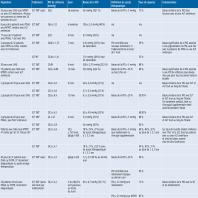

- eTableau 16-1a - Efficacité de la SLT signalée dans les différentes études

- eTableau 16-1b - Efficacité de la SLT signalée dans les différentes études

- eTableau 16-1c - Efficacité de la SLT signalée dans les différentes études

- eTableau 16-1d - Efficacité de la SLT signalée dans les différentes études